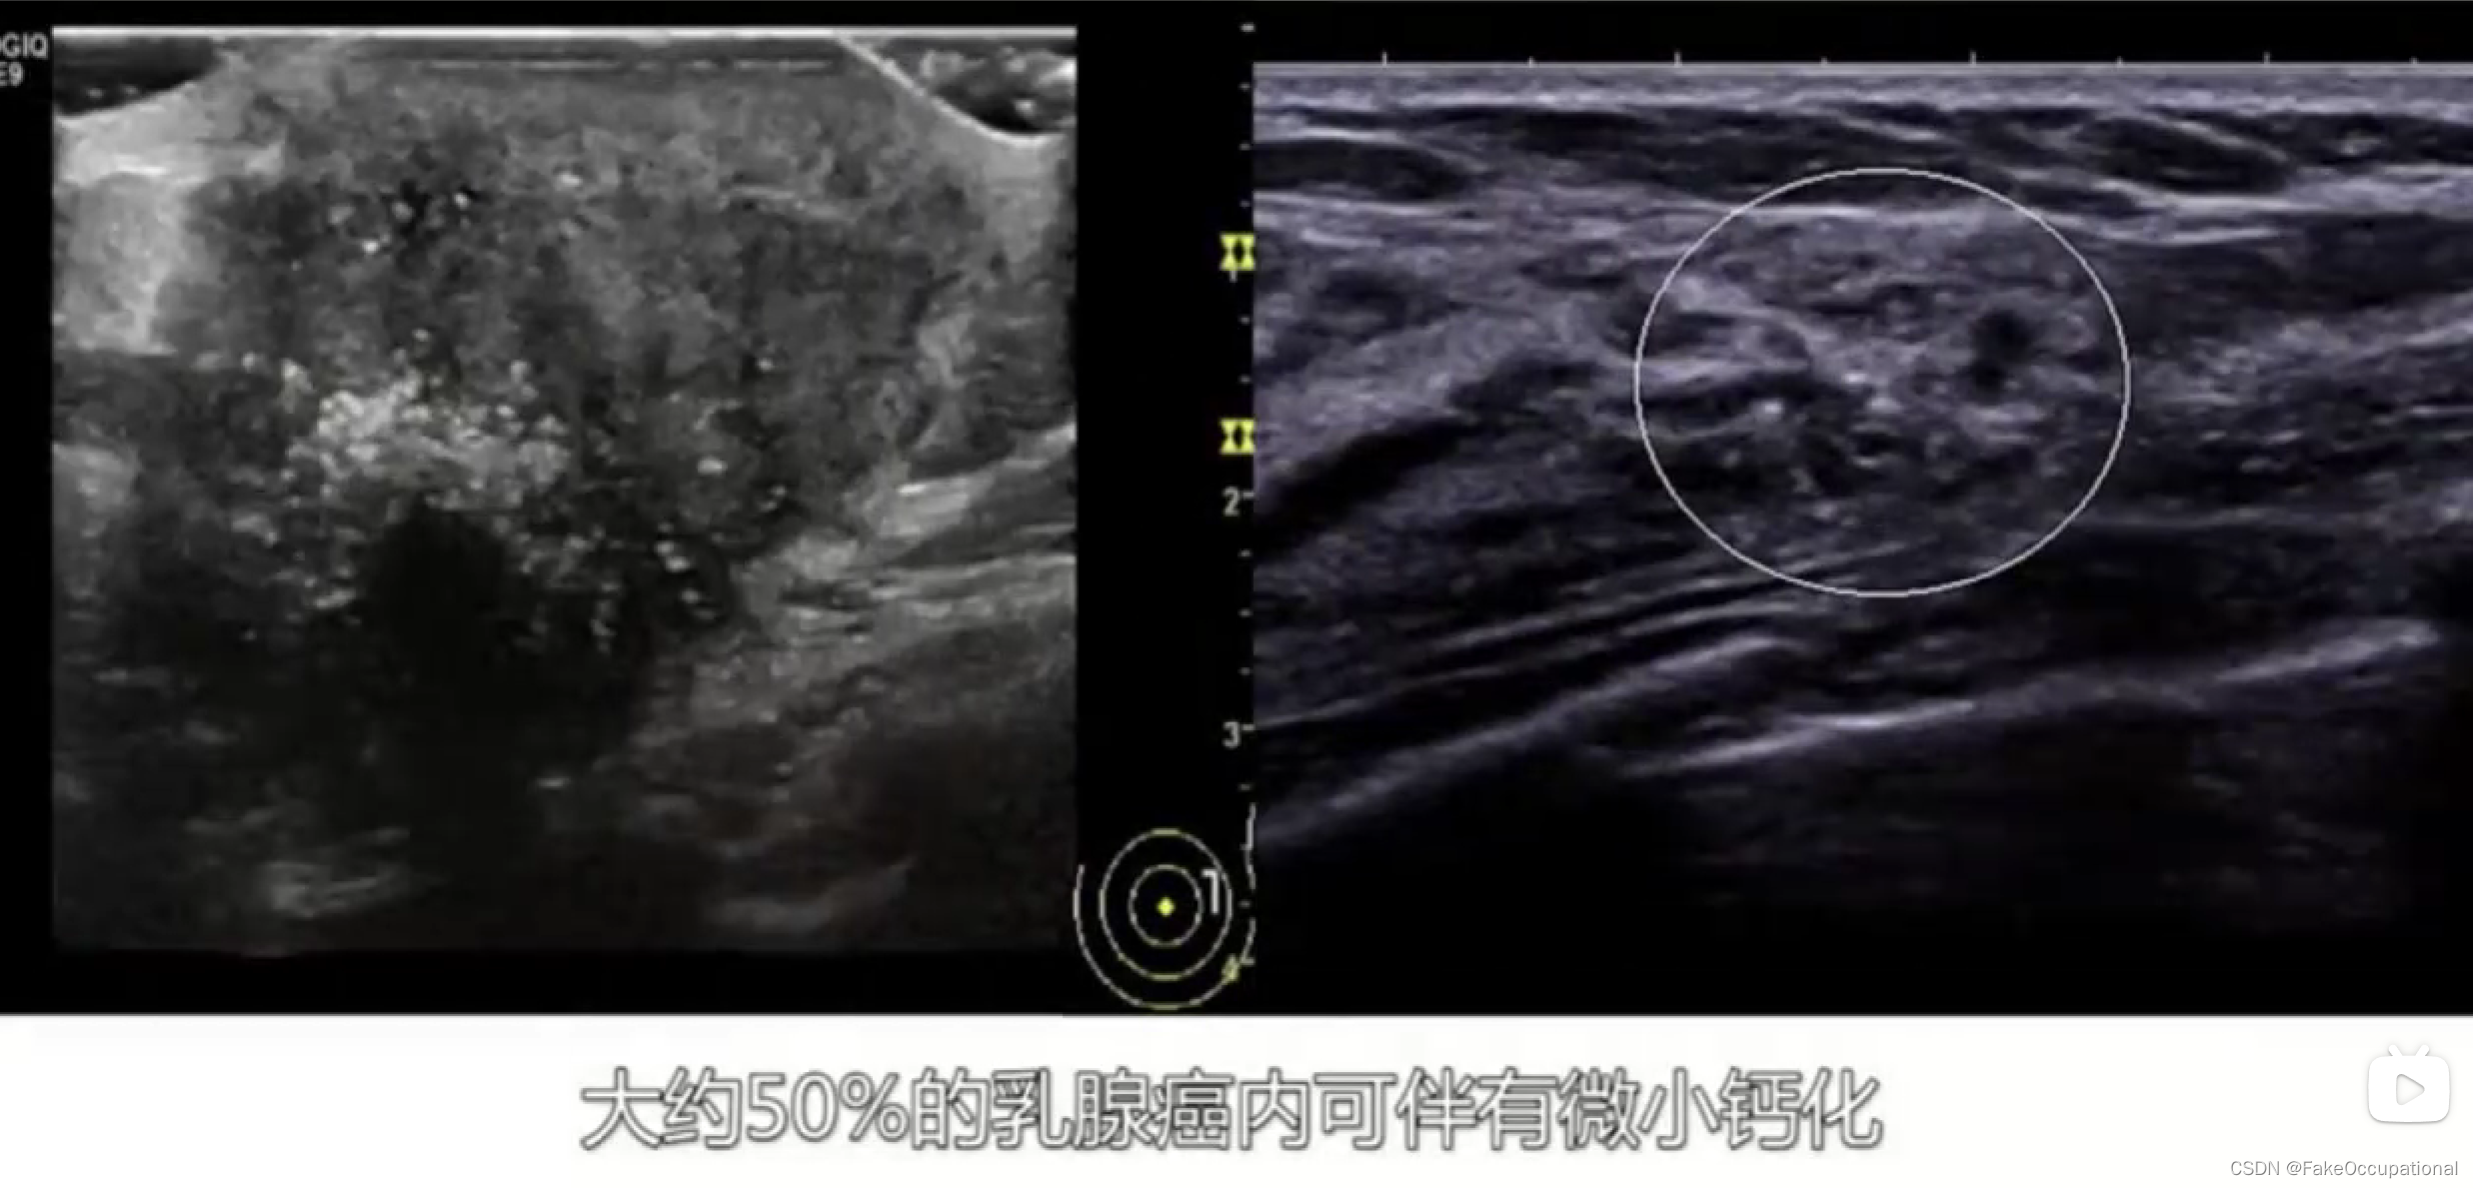

乳腺癌

- 患者18岁,微小癌

- 其理论依据是恶性肿瘤常星离心性生长

- 淋巴结转移